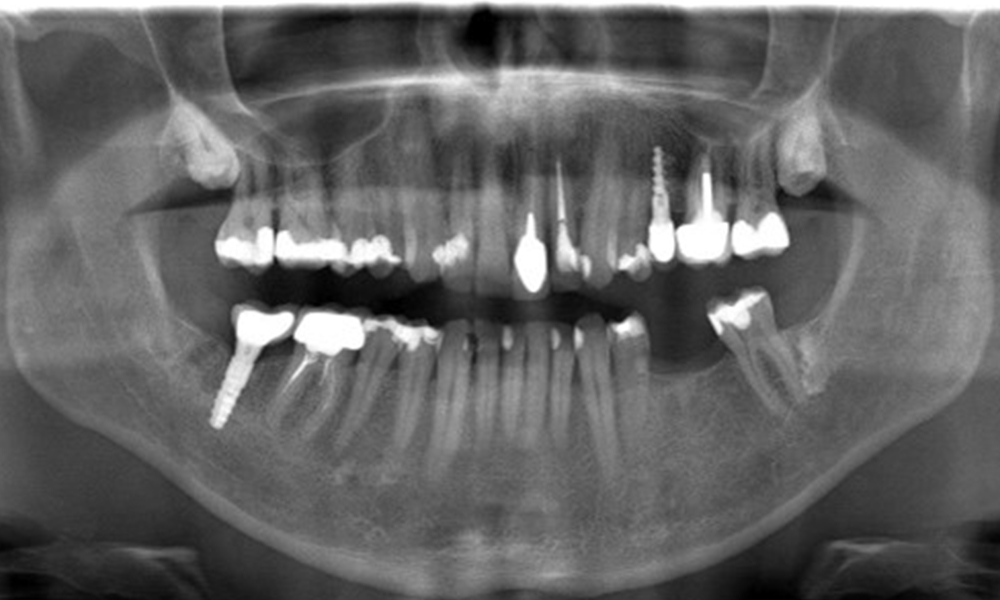

In the medical history, the 55-year-old patient states that he has no systemic disease and is not taking any medication. The patient’s lifestyle is similarly unremarkable. The patient has a few tooth restorations and two implants (2nd and 4th quadrants). On the basis of current findings, gingivitis is identified in an otherwise stable periodontal condition on the reduced periodontium (stage III, grade A).

Previous treatments: dental restorations (non-precious metal/ceramic blend), two implants (2nd, 4th quadrants)

Risk of onset: moderate for peri-implantitis

The patient has no particular risk factors with specific dental implications. The key factor, therefore, is the requirement in terms of oral health. In this respect, good oral health is evident with stable, reduced periodontium. Should evidence of an increase in probe depth compared with the baseline, combined with diffuse bleeding, be found at a check-up appointment, diagnosis using X-ray imaging (dental X-ray) should be undertaken in order to identify peri-implant bone loss at an early stage and intervene accordingly.

On the basis of the stable periodontal and peri-implant situation, it is recommended that the patient should have check-ups every six months.